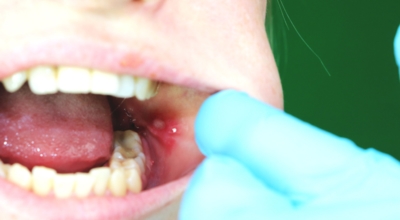

입안 점막이 동그랗게 패여 통증을 유발한다면, 아프타성 구내염을 의심할 수 있어요. 음식을 먹을 때마다 아픈 작은 궤양이 생겼다면, 아프타성 구내염을 의심할 수 있어요. 아프타성 구내염은 빨간색 둘레를 가진 둥근 형태의 흰색 궤양이, 얕은 깊이로 한 개 및 여러 개 생기며 통증을 동반하는 것이 특징입니다. 전 인구의 20~40%가 발병할만큼 통상적으로 나타나는 질환으로 20대, 주로 여성분들에게 많이 나타나며, 일주일 정도면 자연적으로 치유되지만 1~3개월 간격으로 빈번히 재발하는 것이 특징입니다.

까닭은 입 속 점막의 작은 상처나, 바이러스, 세균의 감염, 각별히 수면 부족이나 과로, 스트레스가 축적돼 면역력이 떨어졌을 때와, 비타민 B12 또는 엽산 결핍 시에 많이 생기 다고 알려져 있어요. 흔한 질환이니만큼 자연적으로 치유 되지만, 통증을 동반하고, 궤양의 크기가 커지거나 숫자가 늘어나기도 하기 때문에 연고나 외용제, 가글액 등을 활용해서 증상을 경감시키는 치료를 하기도 해요.